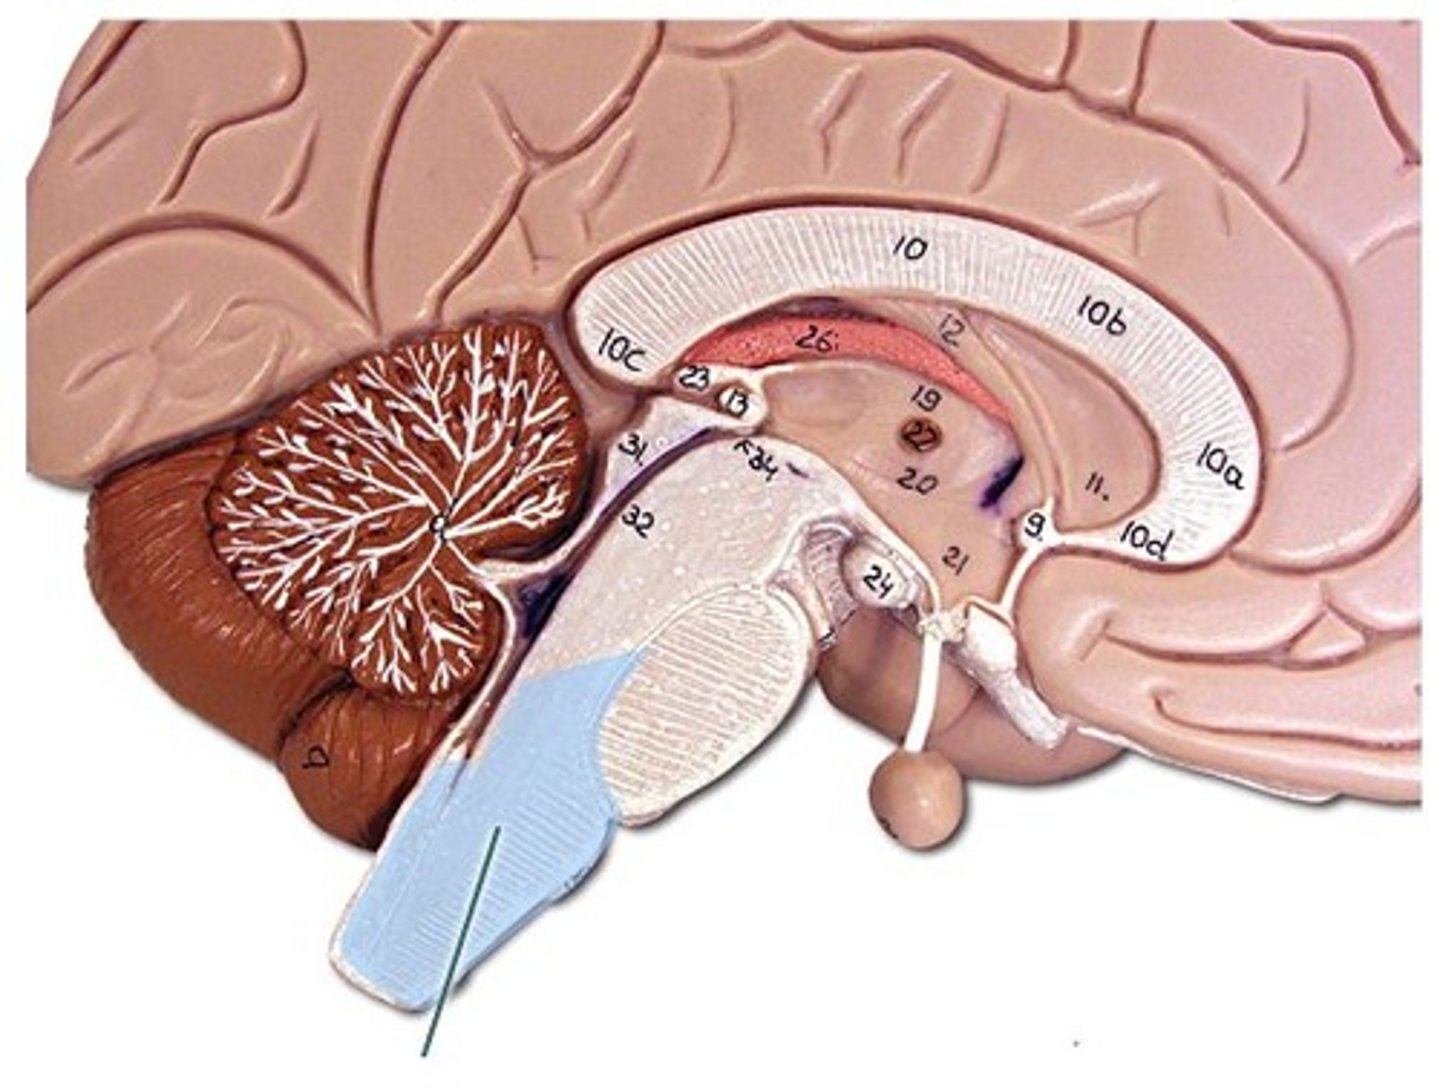

34 Terms

1

New cards

longitudinal fissure

2

New cards

frontal lobe

3

New cards

temporal lobe

4

New cards

parietal lobe

5

New cards

occipital lobe

6

New cards

central sulci

7

New cards

lateral sulci

8

New cards

gyri

9

New cards

cerebrum

10

New cards

corpus callosum

11

New cards

lateral ventricles

12

New cards

3rd ventricle

13

New cards

4th ventricle

14

New cards

cerebellum

15

New cards

thalamus

16

New cards

hypothalamus

17

New cards

midbrain

18

New cards

pons

19

New cards

medulla oblongata

20

New cards

cerebral aqueduct

21

New cards

I.

Olfactory

22

New cards

II.

Optic

23

New cards

III

Oculomotor

24

New cards

IV.

Trochlear

25

New cards

V.

Trigeminal

26

New cards

VI.

Abducens

27

New cards

VII.

Facial

28

New cards

VIII.

Vestibulocochlear

29

New cards

IX

Glossopharngeal

30

New cards

X.

Vagus

31

New cards

XI

Accessory

32

New cards

XII

Hypoglossal